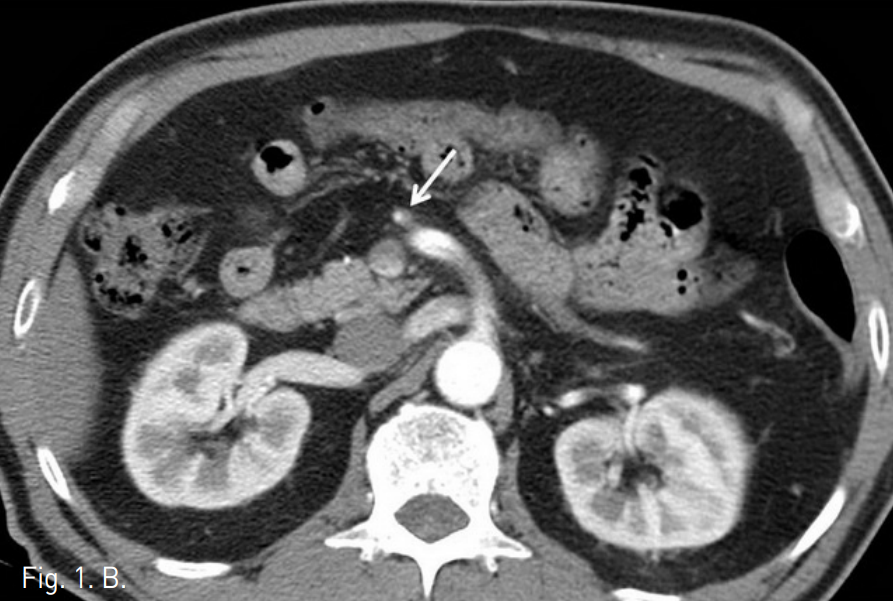

복부 CT에서 상장간막동맥(superior mesenteric artery, SMA)의 박리가 있었으며 중간결장동맥(middle colic artery)의 기시부가 경도로 좁아져 있고 가성 내강과 진성 내강의 혈류가 관찰되었다(Fig. 1). 같은 날 시행한 혈관조영술에서 상장간막동맥 기시부부터 회결장동맥(ileocolic artery) 분지부까지 침범한 동맥박리를 확인 하였다(Fig 2). 이 밖에 복강동맥과 하장간막동맥에는 특이 소견은 발견 되지 않았으나 변연 동맥 여러 곳이 동맥경화에 의한 좁아져 있었다. 소장과 대장의 동맥혈류가 유지되고 있어 스텐트삽입술은 시행하지 않았으며, 수축기 혈압 110mmHg, 심장박동 수 50~60회로 유지하며 보존적 약물치료를 하였다. 환자의 복통은 진정되었으며 7일 후 퇴원하였다. 5개월 후 추적검사로 시행한 복부 CT에서 상장간막동맥의 박리피판이 여전히 관찰되며 진성 내강과 가성 내강의 개통성을 확인할 수 있었고 기타 변연 동맥의 폐색은 없는 것이 확인되었다. 하지만 1년 추적 복부 CT에서는 가성 내강을 따라 혈전이 형성되었고(Fig. 3) 원위부로 혈관 폐색의 소견은 보이지 않았으며 장관의 허혈이나 경색 소견 또한 관찰되지 않았다. 2년 추적 CT에서 상장간막동맥은 정상화되었으며 박리나 동맥류 소견은 관찰되지 않았다.

Fig. 1

A, B. (A) The first abdominal CT angiogram taken in ER. The axial image shows dissection in the proximal part of SMA (arrowhed). Both true and false lumens were patent. (B Mild narrowing at the orifice of the middle colic artery is seen (arrow).